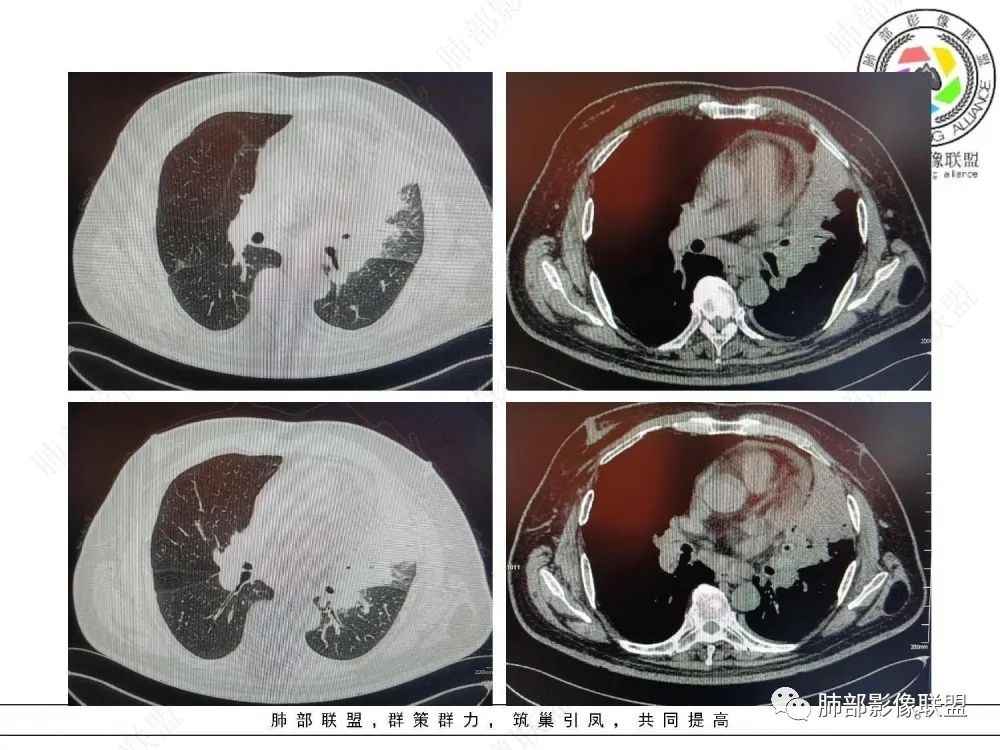

三、影像表现:左肺上叶多发片状高密度影,散在,边缘模糊,支气管壁稍增厚,中轴间质、小叶间隔增厚、有结节感,左肺上叶前段病灶可见胸膜增厚,部分小支气管不能分辨;右肺上叶后段混合磨玻璃结节,边界清,邻近胸膜凹陷;纵膈淋巴结肿大;心包增厚;左侧少量胸水。此外,扫及右侧胸腔内甲状腺肿;左侧肩胛骨旁肌群内脂肪瘤。

四、综合分析:老年男性,以咳嗽咳痰为主要临床表现,无发热,白细胞正常,影像表现为左肺上叶片影,前段结节影、胸膜增厚、部分小支气管不能分辨。左肺上叶中轴间质增厚、小叶间隔增厚、结节感,肺门纵隔见肿大淋巴结,尽管肺部病病灶边缘特征不典型,但高度疑及癌性淋巴管炎这一“次生灾害”却具有相当重要提示意义,而肺癌中最常伴癌淋的就包括腺癌。右肺上叶后段混合磨玻璃结节,边界清楚,张力明显,具有一定特征性,高度指向浸润性腺癌。这对于左肺病灶具有一定程度“助攻”效应。总体而言,本例左肺病灶的诊断关键点在于判断出癌性淋巴管炎。癌性淋巴管炎的结节在外围间质多见,小叶间隔可呈串珠状、结节状增厚,由于出血及水肿,小叶间隔增厚较明显,或呈不规则增厚。有的肺小叶呈多角状阵列。常合并胸水。

肺癌性淋巴管炎(PLC)是肺内、外肿瘤肺转移的一种特殊类型,以 转移癌细胞在淋巴管内弥漫性生长为特征,占肺内转移瘤的6.8%。癌 细胞可播散至肺淋巴管及血管,最终因呼吸衰竭和肺源性心脏病而导致病死亡。临床症状主要为干咳、憋气、体重减轻及低氧血症。本病预后极差,50%~85%的患者生存期3~6个月,临床诊断较困难,常误诊为其它肺间质性病变。 PLC的主要CT征像当中肺纹理异常改变最常见,肺纹理不规则增多、增粗并多发微小结节状更形象解释癌细胞在淋巴管内生长成结节及周围间质增生,导致淋巴管通道堵塞,远处淋巴液回流受阻,通过其它细小交通回流,从而导致肺纹理增粗增多,是PLC较有特征性CT征象,其它疾病所导致的肺纹理增多增粗一般较规则,可为粗细不均或受牵拉变形却极少出现结节状增粗并呈串珠状排列。小叶间隔不规则增厚并多发小结节也是因为小叶间隔淋巴管癌细胞生长及淋巴管通道受阻扩张所致,虽然小叶间隔结节状增粗,但小叶结构不变形是PLC较为特征的CT表现,肺纤维化、 肺水肿、肺胶原病及结节病等肺间质性病变中较少见小叶间隔结节状增粗,而且它们一般导致肺小叶结构变形。肺小叶内间质增生及(或)核心小结节无明显特异性,其表现与特发性肺纤维化、 尘肺及结缔组织病及其它可导致肺间质性纤维化疾病的小叶内间质增厚相类似。PLC导致的胸膜增厚也有一定特征,一般累及胸膜范围较广,程度轻,密度较淡, 部分呈花边样改变,以叶间胸膜较常见,绝大部分病例叶间胸膜受累呈轻度增厚并沿表面排列多发微小结节,伴随PLC其它征象,未见单独存在。肺内结节及 (或)小斑片状实变影无特异性, 与肺结核、炎症、肺血行转移瘤及类风湿等结缔组织病的肺部表现相似,也可能为合并血行转移及肺部感染。纵膈及肺门淋巴结肿大、胸腔及心包积液均无特异性,曾有文献报道,单侧叶间裂积液对PLC的诊断有相对特异性, 因单侧的叶间裂积液主要是由于胸膜下淋巴管堵塞,淋巴回流受 阻所致,可提示PLC的存在。